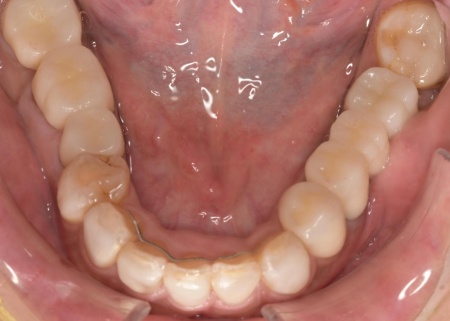

矯正期間終了後は、被せ物による治療に移行します。

上顎の前歯2本ずつと奥歯4本(左右中切歯・第2小臼歯・第1大臼歯)、下顎の奥歯7本(左第1小臼歯・左右第2小臼歯・第1大臼歯・第2大臼歯)には、見た目が自然なセラミックの被せ物「ジルコニアクラウン」を装着しました。

ジルコニアは、金属を使わないため金属アレルギーの心配が少ない点、人工ダイヤモンドと呼ばれるほどの強度をもち噛む力の強い奥歯にも適している点がメリットです。

加えて、上前歯4本(左右側切歯・犬歯)と下前歯5本(左右中切歯・側切歯・右下犬歯)は、ダイレクトクラウンによる修復を行いました。

ダイレクトクラウンとは、レジン(樹脂)を用いて直接歯の形を作り上げていく治療方法です。

歯を削る量が少ない、色や形を細かく調整しながら仕上げられる、治療後は必要に応じて微調整がしやすいなどのメリットがあります。

最後に、見た目や噛み合わせに問題がないかを確認し、治療を終了しました。